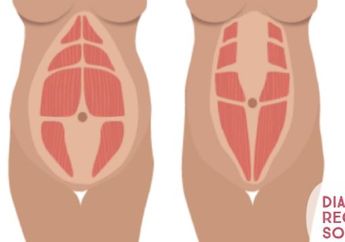

7 Tahun yang lalu - Diastasis Recti sebetulnya bisa diatasi, namun ada baiknya kamu melakukan konsultasi dengan ahli.